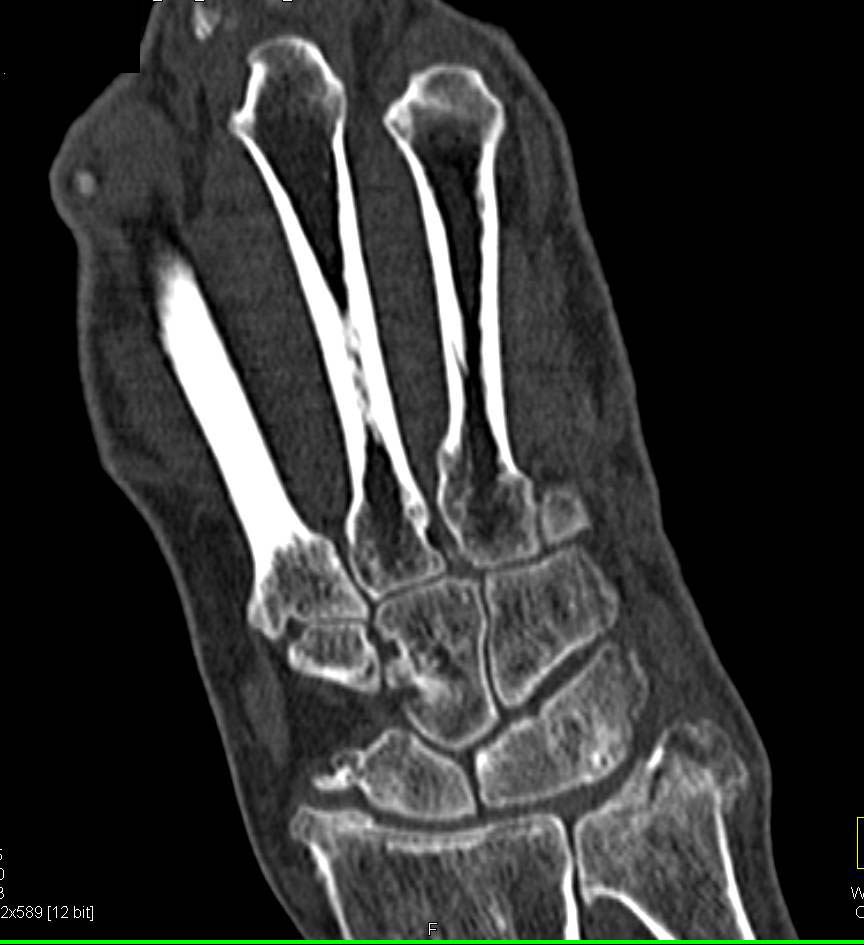

Hip Dysplasia with Shallow Acetabulum and Open Reduction Internal Fixation (ORIF)